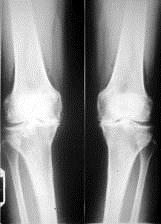

问题 病历摘要: 患者女性,65岁,双膝关节疼痛畸形,伸直受限10分钟,加重3个月。查体:双膝关节呈内翻畸形,双膝关节屈曲90受限,伸直受限,实验室检查正常,癤线见图: 患者行全膝关节置换术后3周出现左膝关节红肿、疼痛难忍,有脓肿,抽出约2ml脓性渗液,ESR↑,C-反应蛋白↑,WBC正常,脓培养为革兰氏阳性菌,该患者最有可能并发什么?

选项 A、左髌前脂肪液化坏死感染 B、左髌前滑囊感染 C、左膝切口皮下感染 D、左膝关节假体感染